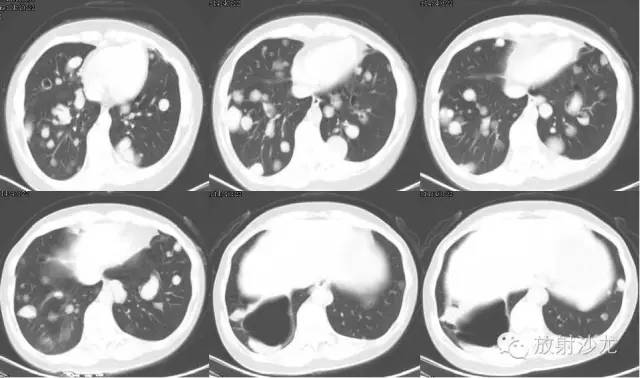

【影像表现】

双侧胸廓对称,纵隔居中。双肺可见散在多发大小不等类圆形软组织密度影,密度欠均,边界较清,最大者约5.32cm*7.88cm*6.75cm,右肺中叶、下叶可见一不规则形透亮影,内无肺纹理,纵隔未见明显肿大淋巴结,胸膜无增厚,右侧胸腔内可见弧形液体密度影。

右肺中下叶肺大泡

右侧胸腔积液